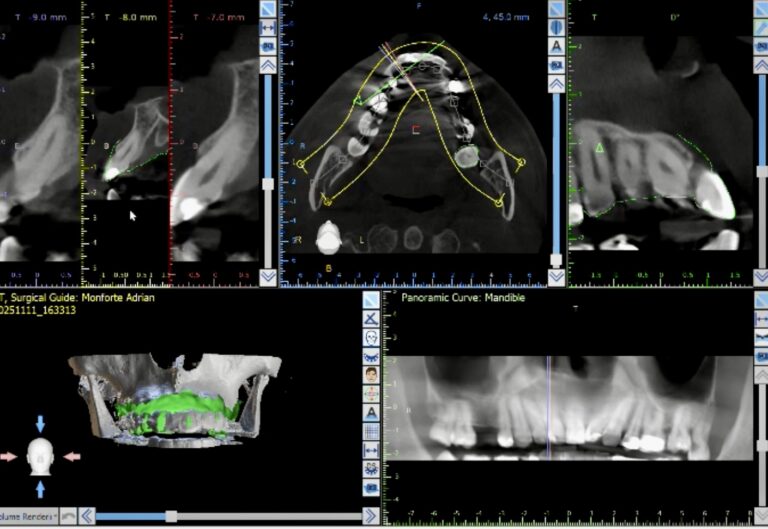

Guided surgery isn’t a specialized technique reserved only for experts or complex cases. Recent clinical evidence suggests that guided surgery can improve consistency across practitioners. Some studies indicate that novice surgeons may achieve accuracy comparable to more experienced surgeons under controlled study conditions [1]. Complex cases may become more manageable, and many practitioners can reach proficiency relatively quickly with proper guidance and training. This article examines what current clinical evidence shows about guided implant surgery and why it is increasingly used in modern implantology.

Different guided workflows have distinct applications and trade‑offs.

Fully Guided Surgery

Uses full surgical templates that restrict the drill throughout the osteotomy and implant insertion.

Clinical evidence suggests that fully guided workflows lead to very low deviations when properly planned and executed, and may be especially valuable in critical or anatomically demanding cases.

However, fully guided systems may be more sensitive to guide fit, drill tolerances, and patient factors (e.g., limited mouth opening).

Dynamic Navigation

Real-time tracking and visualization of the drill relative to the plan.

In prospective full-arch trials, navigation produced good accuracy even in complex, immediate-loading cases [3].

Highly flexible, but requires training, calibration, and introduces its own possible sources of error.